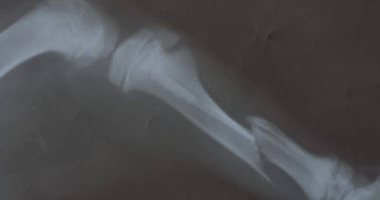

جراحة ناجحة لتثبيت عظام ساق كلب عمره 3 شهور تعرض لحادث سيارة بالغربية

يأتي ذلك استمرارا لمجهودات أطباء مركز طب وجراحة الحيوانات الأليفة، بديوان عام مديرية الطب البيطرى فى تقديم خدمه متميزه لعلاج الحيوانات الأليفة وحالات الطواريء وتم استقبال الكلب في العيادة وتبين إصابته بكسر في عظام الساق اليمني بعد تعرضه لحادث سيارة. وقام بإجراء العملية الفريق المكون من الدكتورة سحر...